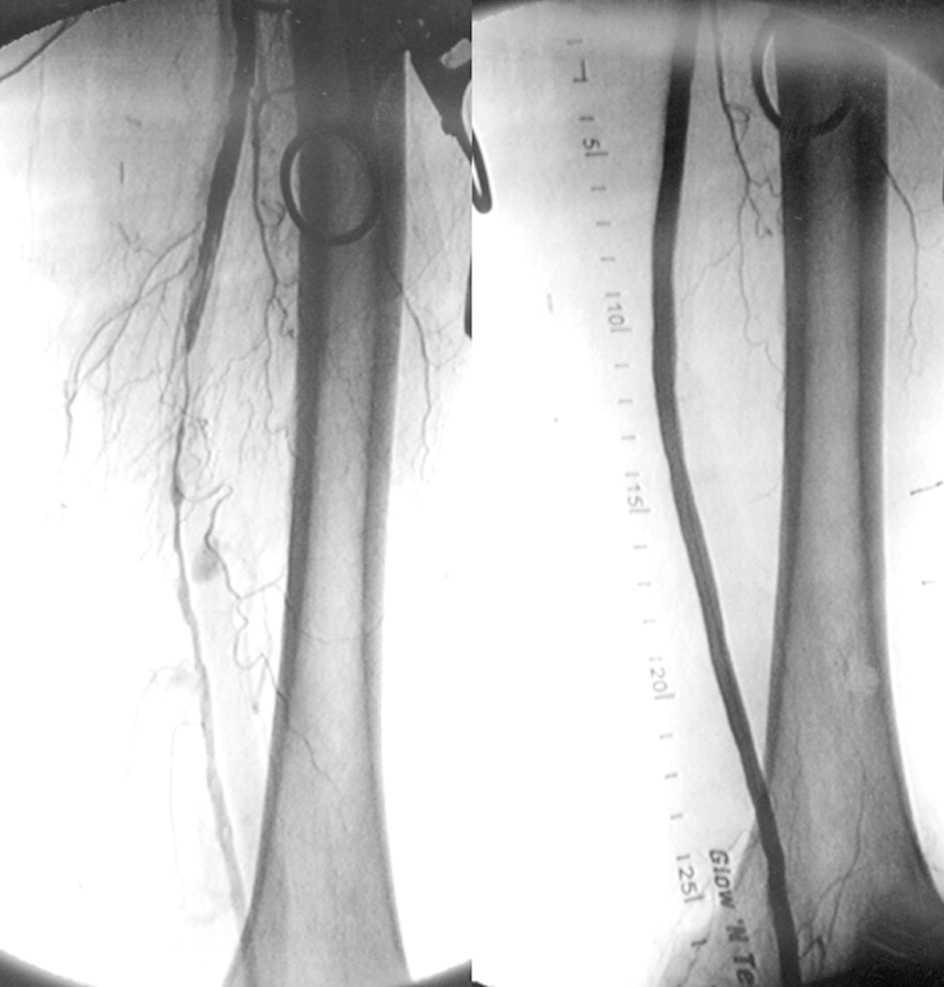

Tratamiento quirúrgico o endovascular de  la isquemia severa de miembros inferiores

08 noviembre 2022

En pacientes con isquemia crónica y severa que tenían una vena safena adecuada para la revascularización quirúrgica, los resultados fueron significativamente mejores en el grupo quirúrgico que en el grupo de tratamiento endovascular. Para aquellos pacientes que carecían de una vena safena adecuada para la cirugía, los resultados en los dos grupos fueron similares. New England Journal of Medicine, 7 de noviembre de 2022.